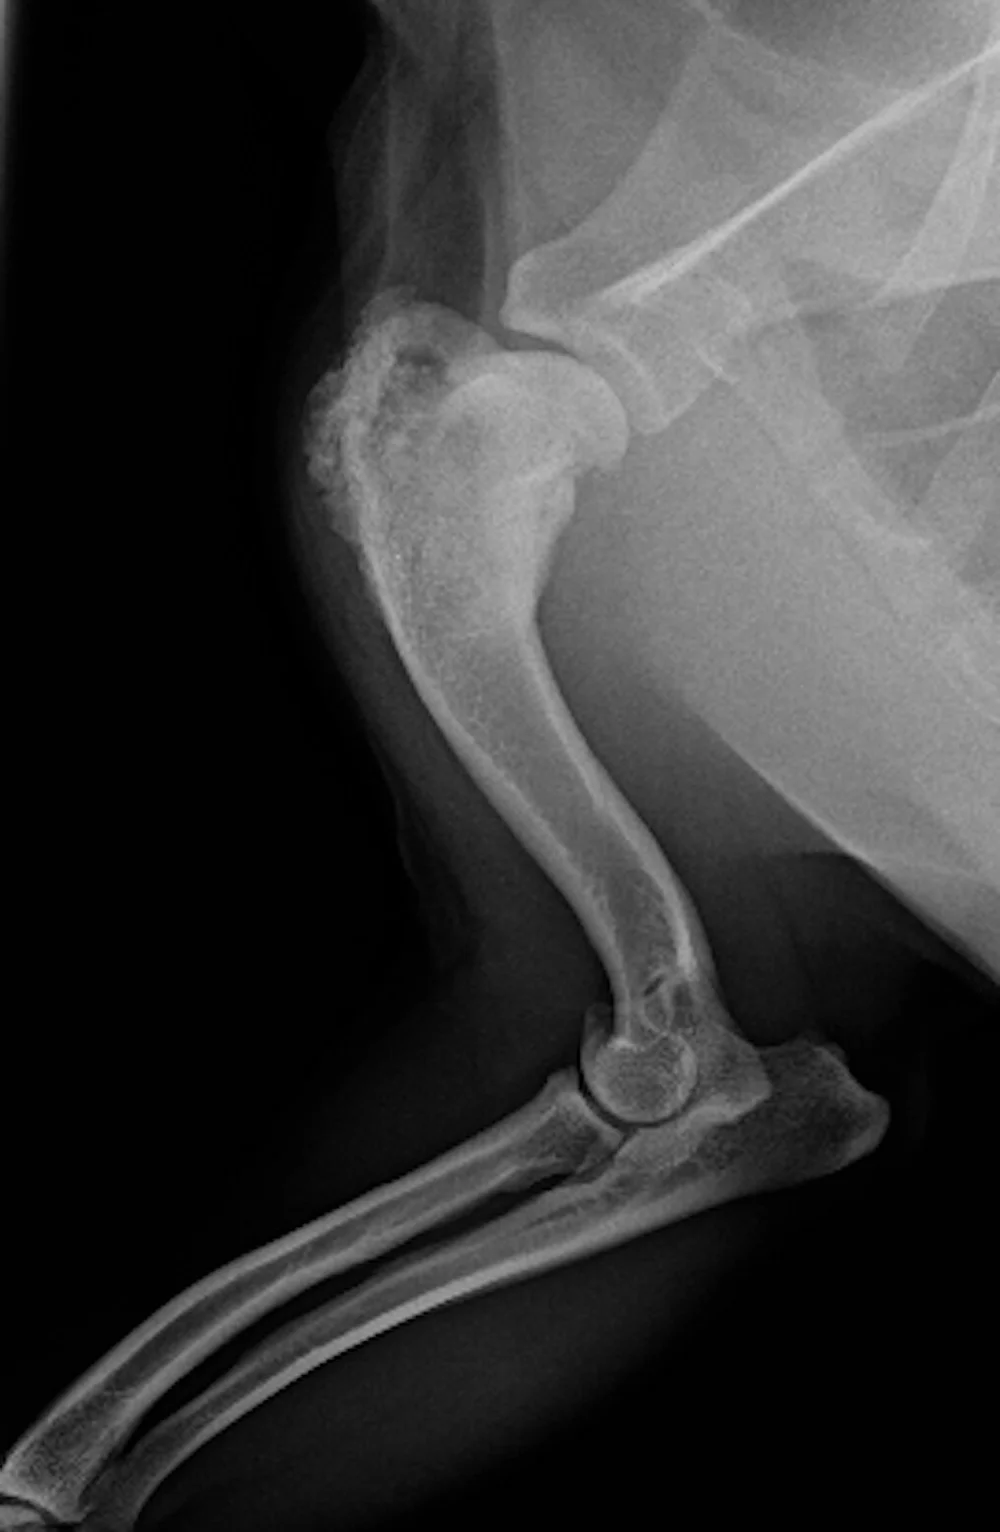

Osteosarcoma is the most common bone tumor is dogs accounting for 85 of all bone tumors. Breast cancer had the highest. A normally energetic dog may begin fatiguing after walking or playing.

And that is with chemotherapy. Most cases of canine osteosarcoma about 90 have undergone micrometastasis by the time they are diagnosed making this type of cancer difficult to cure. In a period of three months the tumor can overtake the dogs limb and weaken it.

Osteosarcoma can occur in any bone in the dogs body but is more likely to occur in their limbs. Bones of the appendicular skeleton thoracic and pelvic limbs are most commonly affected. Answer 1 of 14.

Osteosarcoma accounts for approximately 85 of bone tumors in dogs. Whether your dog has STS OSA or any other cancer this book will help. A dog that has been amputated and has had chemotherapy can expect to live for 10 to 12 months.

Cigarette smoke gas exhaust and water may contribute to cancer development. The metastasis rate for high-grade STS is much higher. Unfortunately most dogs with a bone lesion will have osteosarcoma 80.

Sometimes bone cancer makes a sudden appearance as a lump in the leg or in worst case scenario as a pathologic fracture. To name just a few. With pets living longer than ever cancer has become a diagnosis that we see more commonly in older dogs.